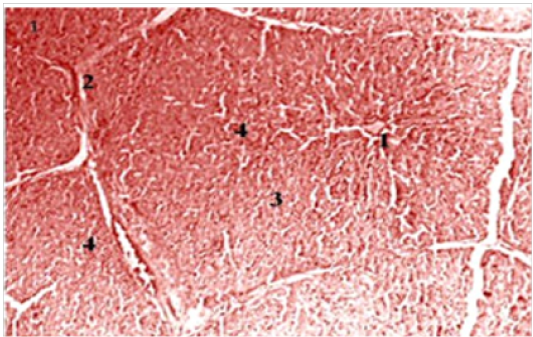

Liver parenchyma of broiler chickens at high magnification (H& E X100).

1- Hepatocyte. 2- Central vein 3 - sinusoidal capillary. 4 - Central parenchyma nucleus